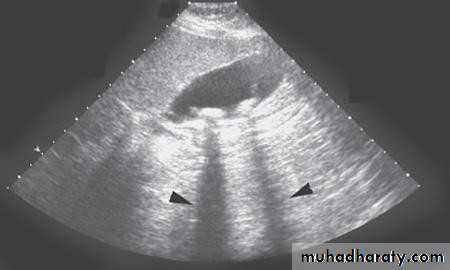

• Ultrasonography:

• Non-invasive• Standard initial imaging for patient suspected to

• have a gall stone and in jaundiced patients.

• Ultrasonography:can demonstrate

• Gall stones• GB size, thickness of its wall, presence of inflammation around it, pericystic edema.

• Size of CBD, occasionally stones in it.